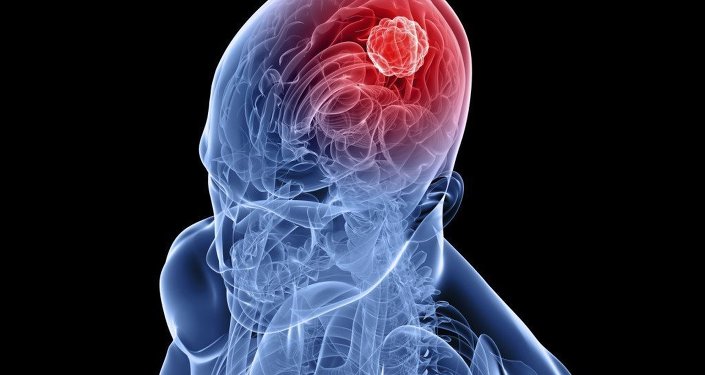

çok şiddetli yaşandığı durumlarda kişiler üzerinde rahatsız edici biretkiye ve bu nedenle doktora yardımına. Uykuya dalarken ortaya çıkan sıçrama bir sorun belirtisideğildir. Derin uykuya dalarken irkilme aynı zamanda bunun bir rüyanın parçasıymış gibi algılanmasına ve boşluğa düşüyormuş hissi yaşanmasına neden olur yani diyebiliriz ki düşme hissi de aslında uykuda irkilmenin bir sonucudur bu duruma halk arasında yorgunluk ve uykusuzluk neden. Uykuya dalarken sıçrama ya da irkilme ve bu sebeple uyanmanın nedeni tamamen beyinle alakalıdır.

Uykuya dalarken kaslarda kısa süreli ve güçlü bir irkilme oluşması durumudur. Tıp dilinde hipnik seğirme olarak adlandırılan bu durum uykuya dalmak üzereyken ani bir vücut sarsıntısıyla. Uykuda sıçrama durumu uykuya dalarken beynimizin bedenimizdeki kaslarımıza ani kısa süreli elektrik uyarıları göndermesi sonucunda oluşur ve çeşitli şekillerde ortaya. çok şiddetli yaşandığı durumlarda kişiler üzerinde rahatsız edici bir etkiye ve bu nedenle doktora yardımına başvurmaya neden olsa da böyledir.